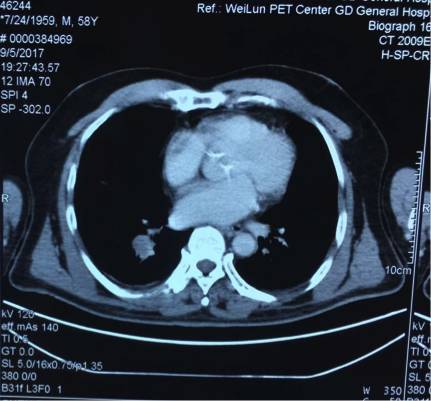

5. 2017-9-5广东省人民医院PET提示:右肺下叶肿物2.8*2.7cm,SUV 22.3,双侧颈部、双侧气管旁、隆突下、食管旁、右侧肺门淋巴结肿大,代谢升高,考虑为转移灶,右侧肾上腺转移灶,具体结果见下图:

7.目前诊断:右下肺肿瘤cT1cN3M1c IVB期(颈部淋巴结、肾上腺)

(准备行经皮肺穿刺活检时图像)

潘燚医生:首先该患者有症状,因此我不太赞同让患者回去观察。若是没有症状,可能可以让患者过段时间再过来随访。刚才病例汇报最后一点说手术,手术的目的是想取得更多的病理?是否可能比局部淋巴结活检取得组织更大?我觉得活检已经是取了很多的组织进行病理诊断,肺部病灶是不是性质跟其它病灶不同?颈部淋巴结、纵隔淋巴结考虑良性,肺部病灶考虑恶性,我认为再做一个手术没有意义。PET-CT和形态学表现是很一致的,那再做一个手术的意义在哪里?颈部淋巴结再取一次活检,可能还是阴性的结果,意义不大。如果从形态学看,肺部病灶和其它病灶的性质一样,可以用一元论解释,目前没有恶性肿瘤的证据。CT上肺部病灶的形态并不规则,也需要注意。

吴一龙医生这个病例的PET-CT有一个特点,右肺下叶的病灶并不大,2.7*2.8cm,但是代谢非常高,高达22.3。这种小病灶高代谢的病灶,在肺癌患者中比较少见。尤其是代谢值大于20但病灶小的情况很少见。我同意谢主任刚的意见,如果该患者没有肾上腺的病灶,我认为诊断可以到此为止。我们可以看到,肺内的病灶有可能是肺内的淋巴结,我们已经对最大的淋巴结进行了活检,为良性病灶。但是,由于该患者多了肾上腺的病灶,用刚才的说法无法解释,肾上腺不属于淋巴系统。结合既往我们遇到的病例,我们现在有两个办法,我认为对于该患者,观察是一个办法,但是如果漏诊会比较麻烦,如果观察一段时间,下次过来复查提示病灶稍增大,我们如何处理?因此我认为现在我们要明确诊断,需要取病理活检,但是是取肺部病灶还是肾上腺的病灶?